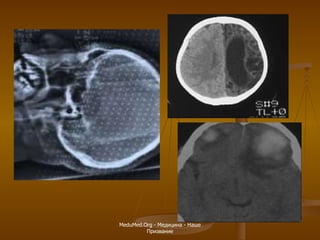

КТ головного мозга в норме Мозжечок Мост Гипофиз Таламус Боковой желудочек Белое вещество Серое вещество Лобные доли MeduMed.Org -  Медицина - Наше Призвание

Современные методики  МР-обследования головного мозга Перфузионная МРТ   -  позволяет получить информацию о кровотоке на капиллярном уровне  Диффузионная МРТ  – позволяет количественно оценить движение молекул воды через мембраны клеток  МР-спектроскопия   – позволяет определить концентрацию метаболитов, таких как  N -ацетиласпартат, лактат, холин, мио-инозитол, в веществе мозга или измерить  pH  ткани мозга  МР-трактография   –  позволяет визуализировать ход проводящих путей головного мозга, например, кортикоспинального тракта  Функциональная МРТ  – позволяет картировать функциональные зоны коры головного мозга, например, двигательную или речевую кору MeduMed.Org -  Медицина - Наше Призвание

Т2-взвешенная томограмма Т 1 -взвешенная томограмма  после введения  Gd Пример контрастирования –  венозная ангиома MeduMed.Org -  Медицина - Наше Призвание